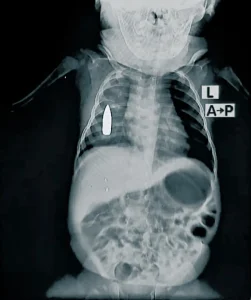

Una radiografía muestra una bala alojada en el pecho de Linda. Los cirujanos determinaron que era demasiado arriesgado extraerla, por lo que tendrá que seguir viviendo con ella. Linda fue alcanzada mientras estaba en la iglesia, cuando un grupo armado abrió fuego contra un helicóptero que se cree está vinculado a la policía. Puerto Príncipe, Haití, enero de 2026.

Sus cuidadores lo llevaron al Hospital con una herida de bala. Recibió un impacto de bala perdida en el pecho mientras dormía una siesta en Jartum, Sudán.

Radiografías de la violencia contra niños y niñas en Sudán

Uno de cada seis pacientes con heridas de guerra atendidos en el Hospital Universitario de Bashair, en el sur de Jartum, Sudán, desde enero de 2024 tiene menos de 15 años, según los datos recabados por Médicos Sin Fronteras (MSF). Muchos han sufrido lesiones por heridas de bala, explosiones y metralla. El personal médico también […]